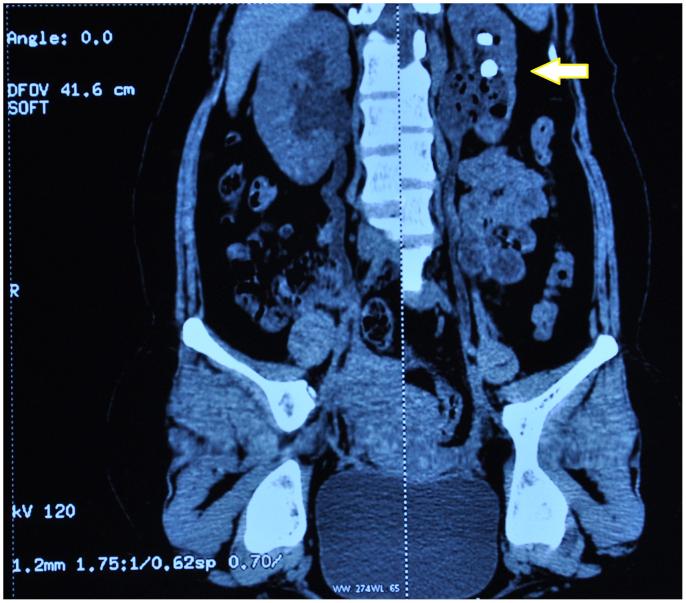

Renal fungal bezoar owing to Geotrichum candidum.

Geotrichum candidum is yeast like fungi that cause infections in immunocompromised patients. We report a case of renal fungal ball with Geotrichum candidum in a 27 yr. old women post-partum. This case to our knowledge is the first case of renal fungal bezoar due to Geotrichum candidum reported in India.